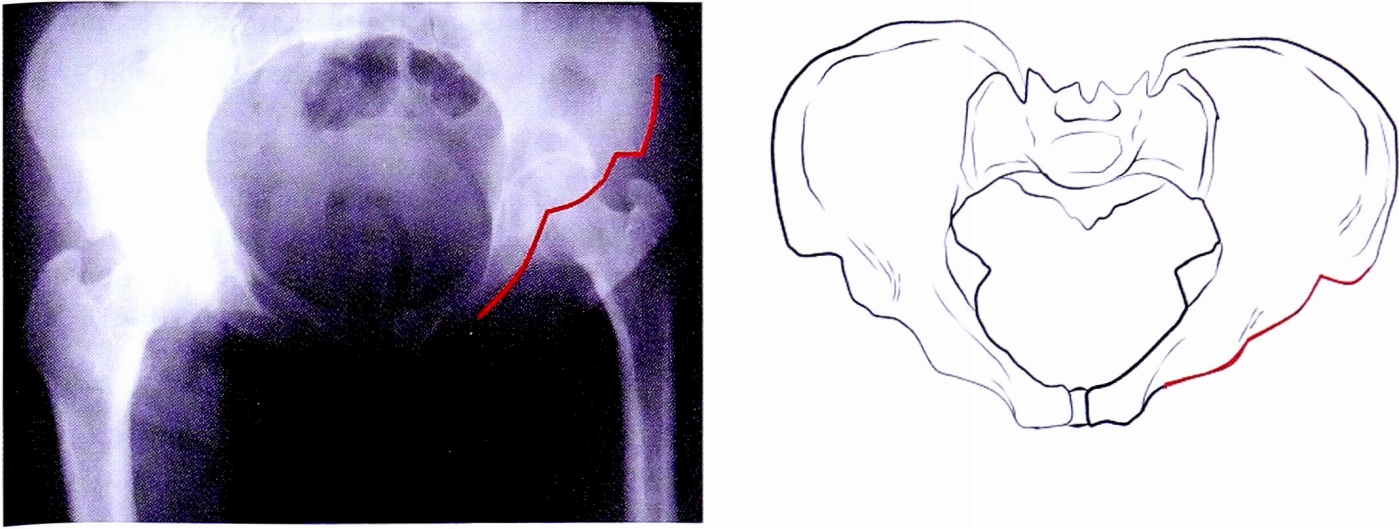

Каудальная обзорная рентгенограмма (Inlet) позволяет выделить зоны, которые соответствуют анатомическим структурам вертлужной впадины: передняя стенка и передняя колонна (рис. 9), задняя колонна (рис. 10).

На уровне головки бедра эта часть линии соответствует передней стенке.

Рис. 9. Контуры передней колонны на рентгенограмме в каудальной проекции и на схеме.

Fig. 9. Anterior column brim on inlet pelvic X-ray and on schematic pelvis.

Рис. 10. Контуры задней колонны на рентгенограмме в каудальной проекции и на схеме, также определяются контуры большой и малой седалищной вырезок.

Fig. 10. Posterior column brim on inlet pelvic X-ray and on schematic pelvis.